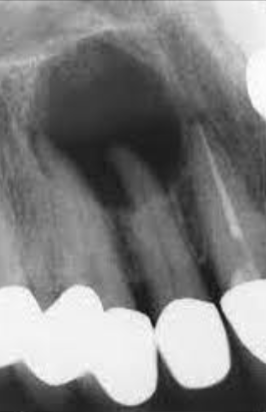

Evaluate #30

Widened PDL

Pulpal Disease

Evaluate #31

Normal PDL

Superimposed Anatomy

Notice other radiographic Features?